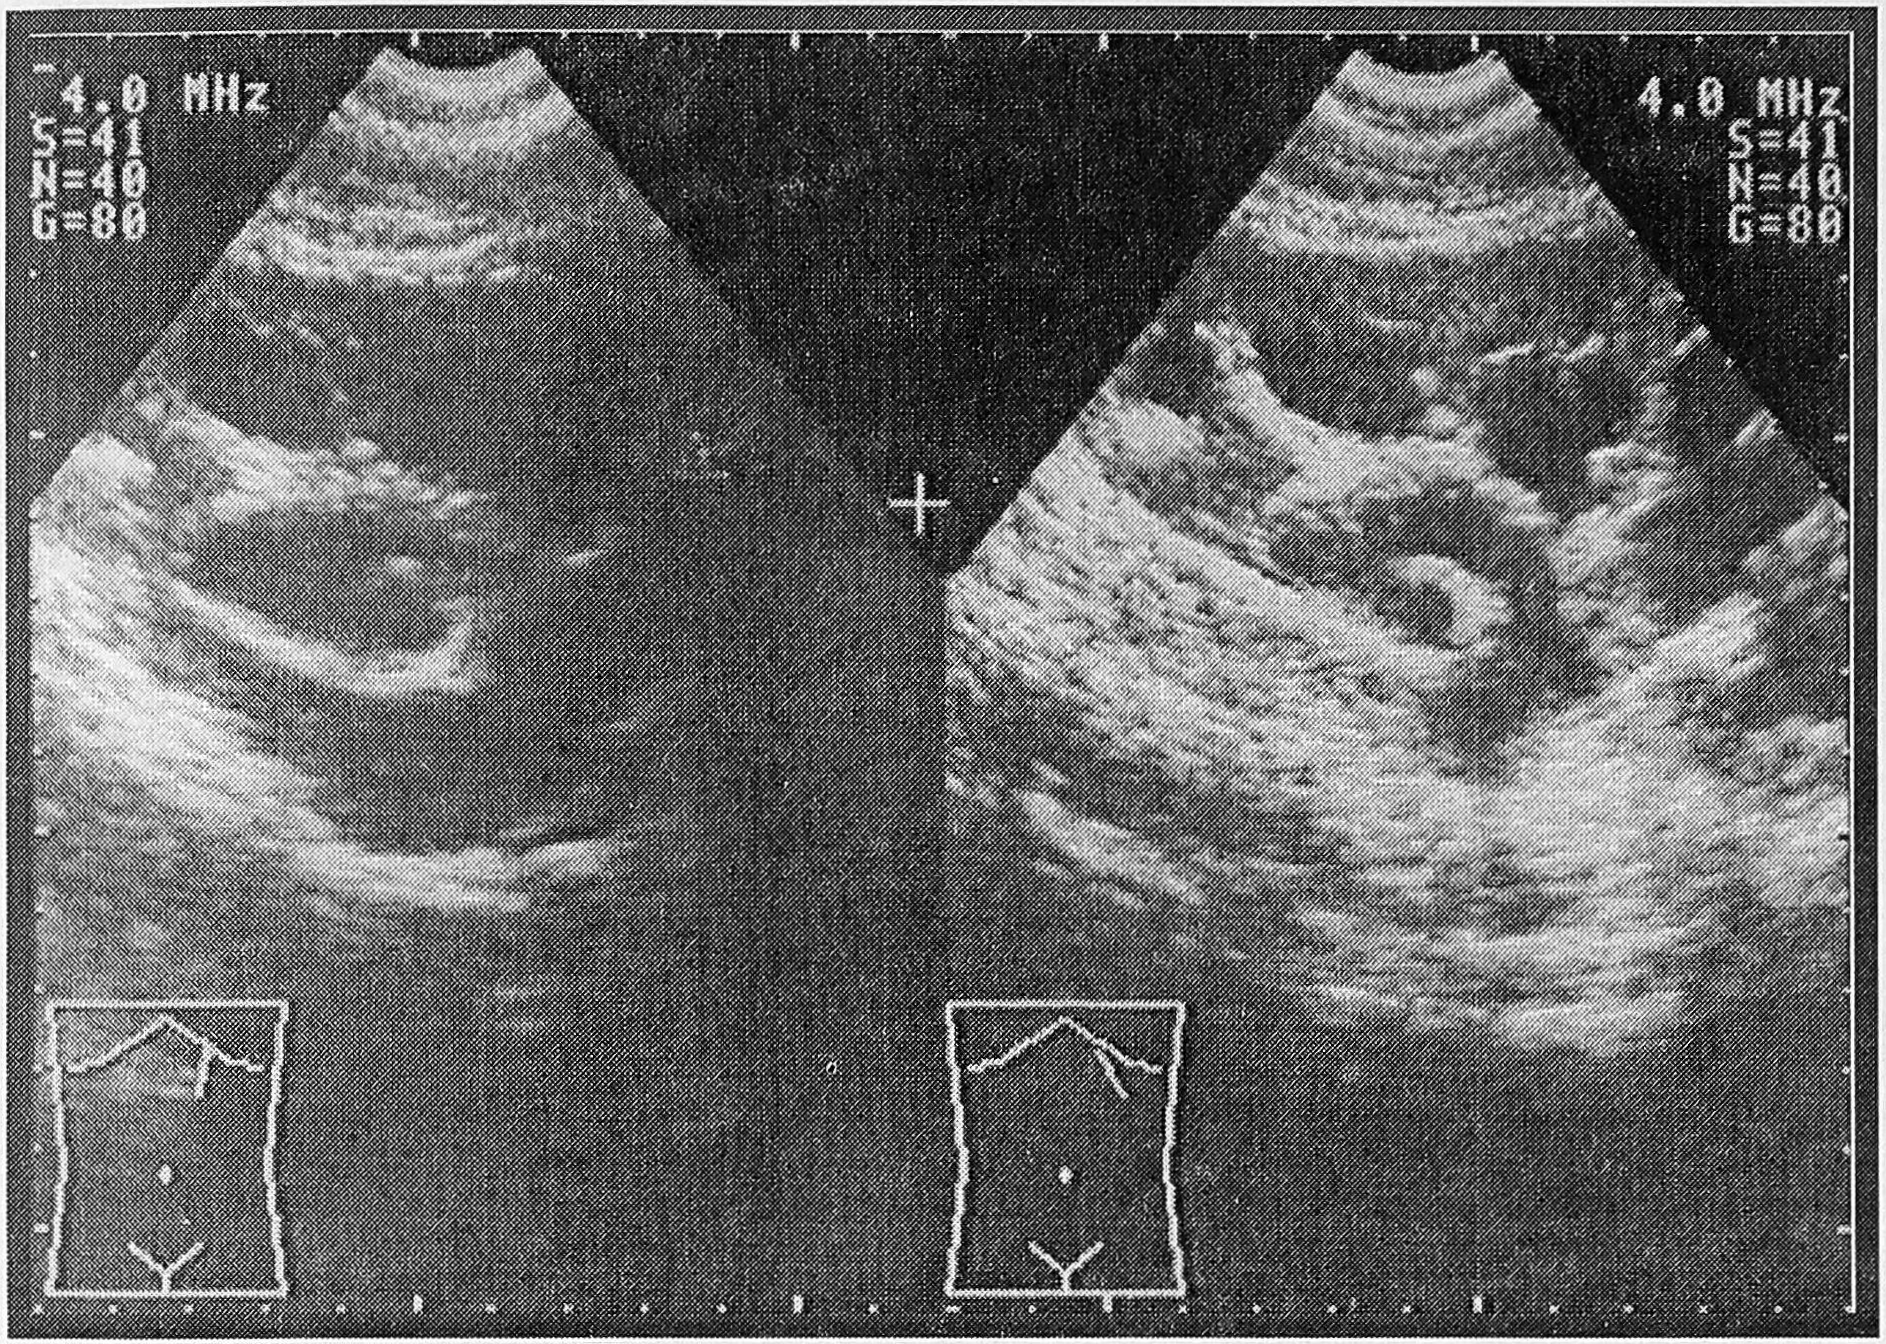

Рис. 2. Сканограмма почки при ятрогенном повреждении мочеточника (3-е сут. после перевязки нижней трети левого мочеточника).

В стандартный набор исследований, необходимых для уточнения диагноза, входит экскреторная урография, ретроградная уретеро-пиелография, хромоцистоскопия, ультразвуковое исследование забрюшинного пространства.

В большинстве случаев экскреторная урография дает представление об уровне и характере повреждения, тогда как хромоцистоскопия только о его локализации.